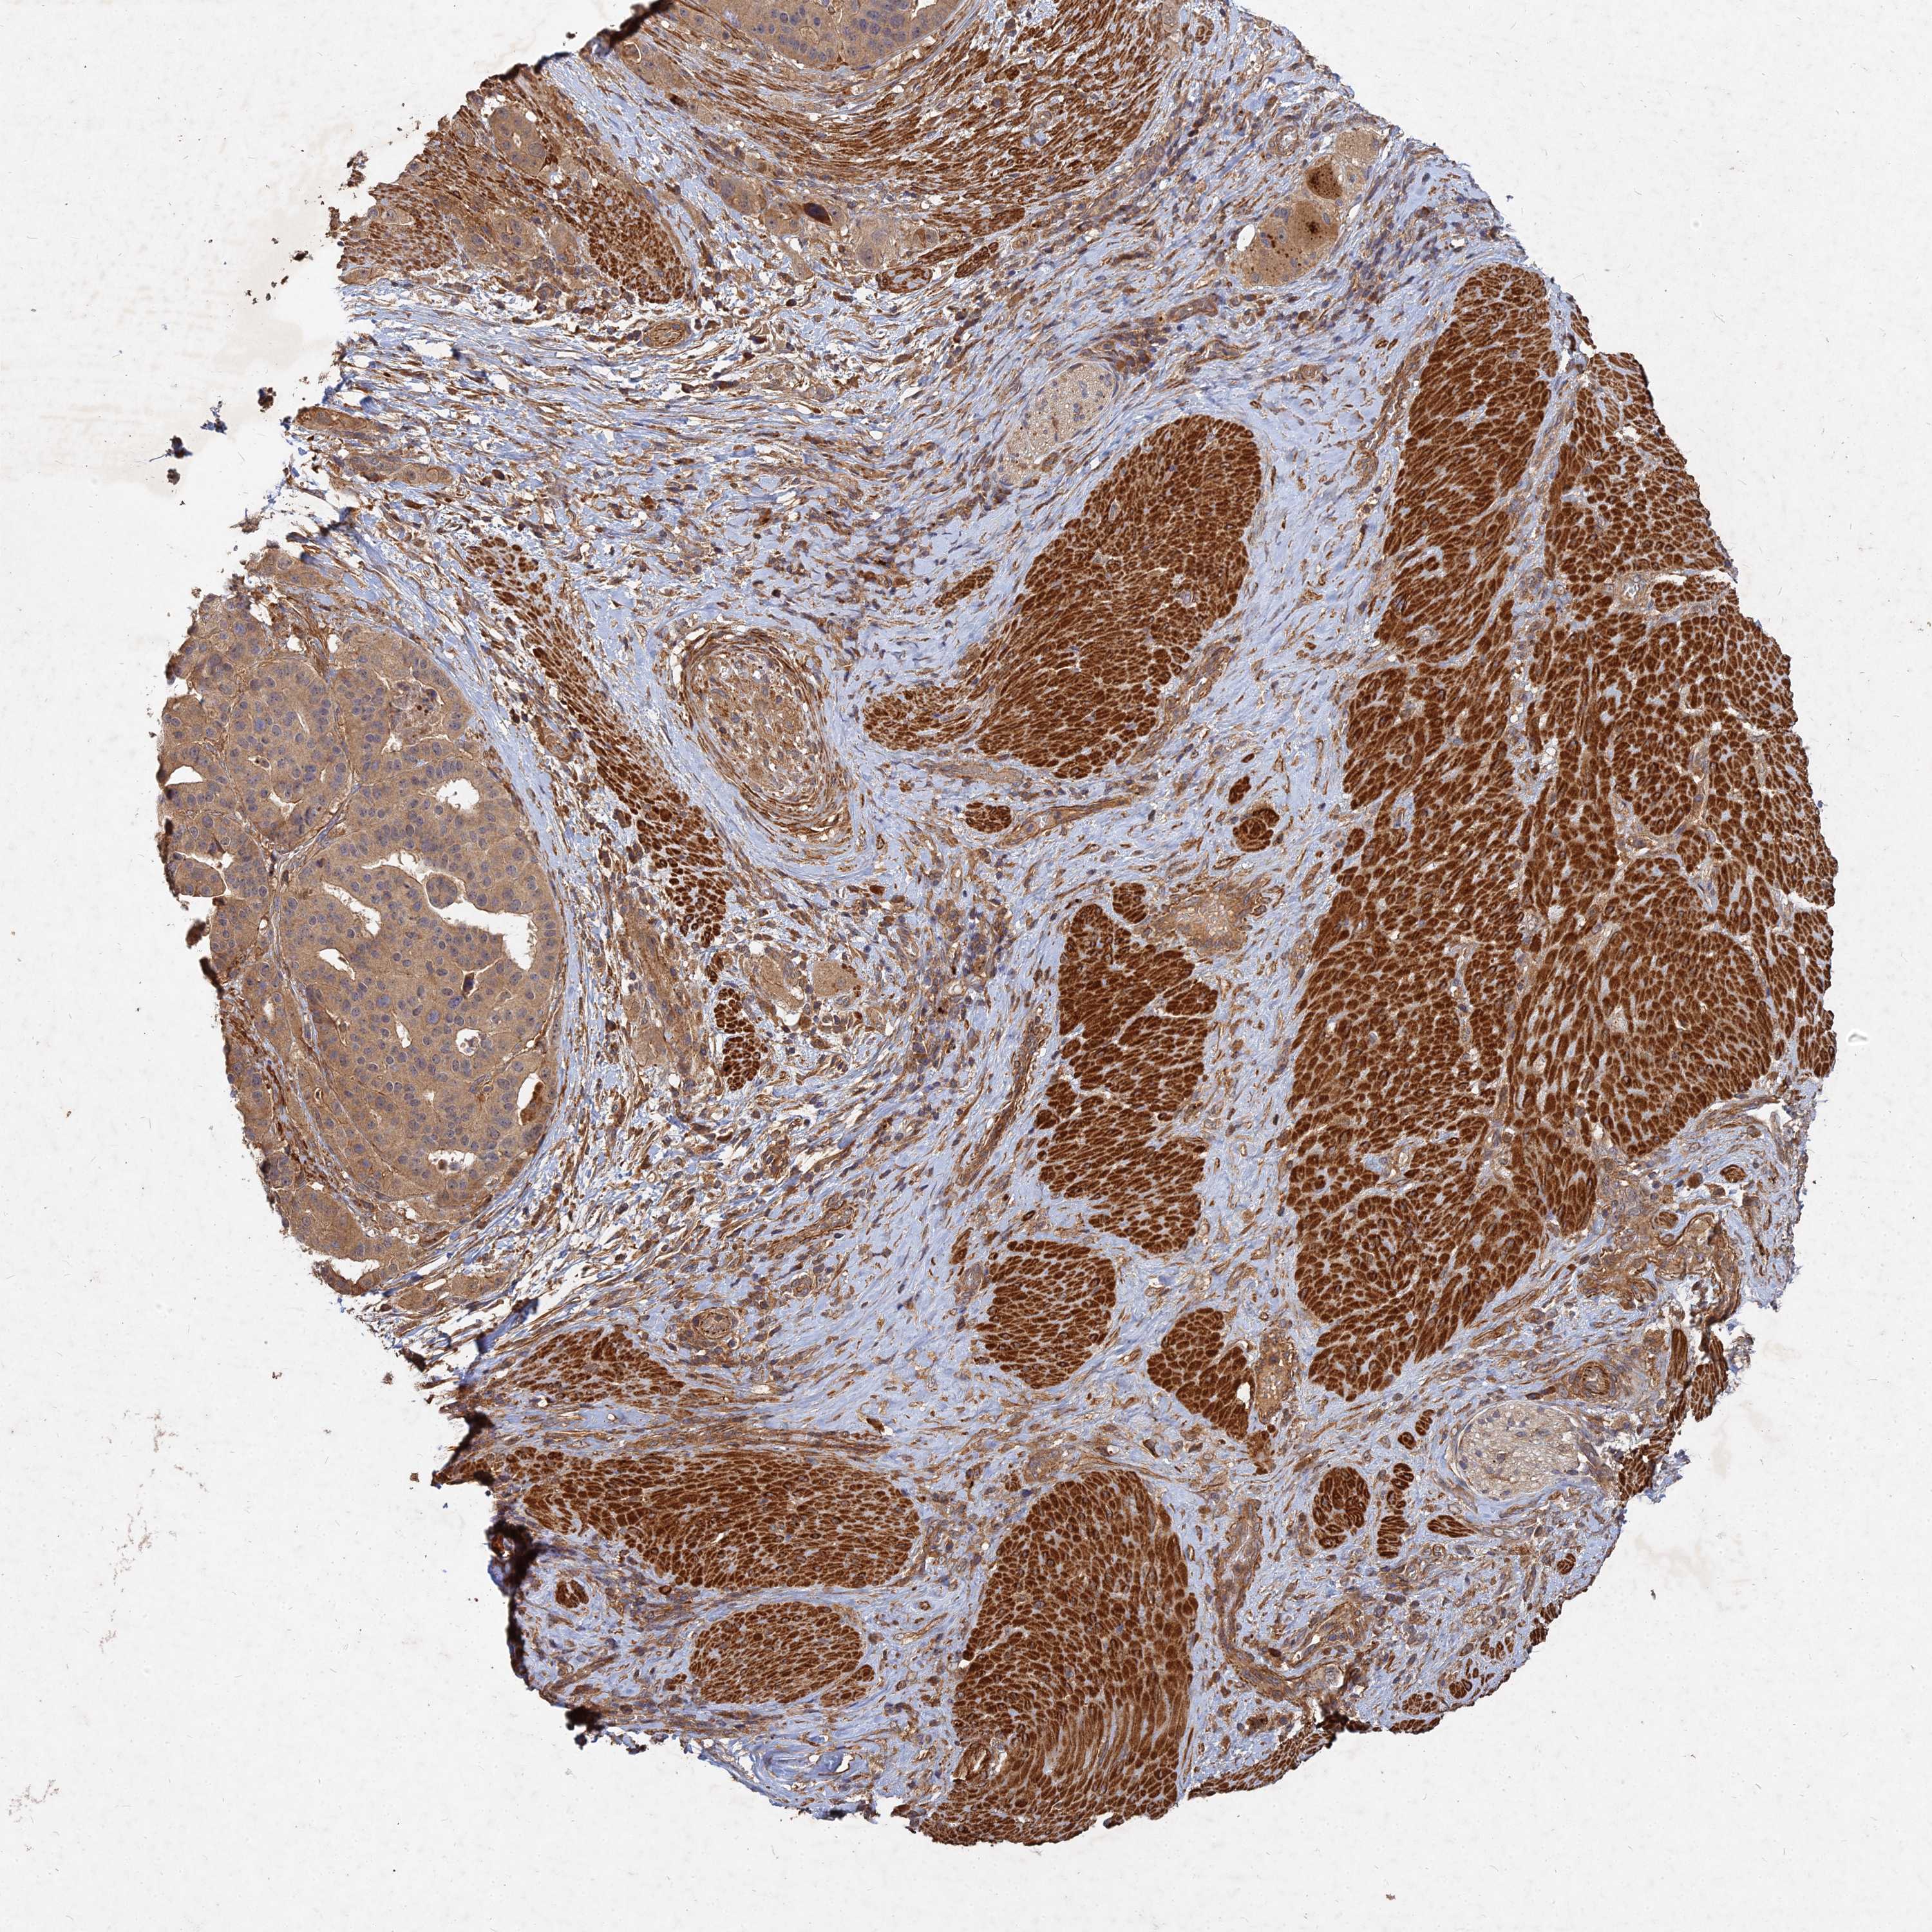

STOMACH CANCER - Protein expressioni

A mouse-over function shows sample information and annotation data. Click on an image to view it in a full screen mode. Samples can be filtered based on level of antibody staining by selecting one or several of the following categories: high, medium, low and not detected. The assay and annotation is described here.

Note that samples used for immunohistochemistry by the Human Protein Atlas do not correspond to samples in the TCGA dataset.

Antibody stainingi

Antibody staining in the annotated cell types in the current human tissue is reported as not detected, low, medium, or high, based on conventional immunohistochemistry profiling in selected tissues. This score is based on the combination of the staining intensity and fraction of stained cells.

Each image is clickable and will lead to virtual microscopy that enables deeper exploration of all samples and also displays staining intensity scores, fraction scores and subcellular localization as well as patient and tissue information for each sample.

Antibody HPA045161

Staining

High

Medium

Low

Not detected

Intensity

Strong

Moderate

Weak

Negative

Quantity

>75%

75%-25%

<25%

None

Location

Nuclear

Cytoplasmic/membranous

Cytoplasmic/membranous,nuclear

Adenocarcinoma, NOS